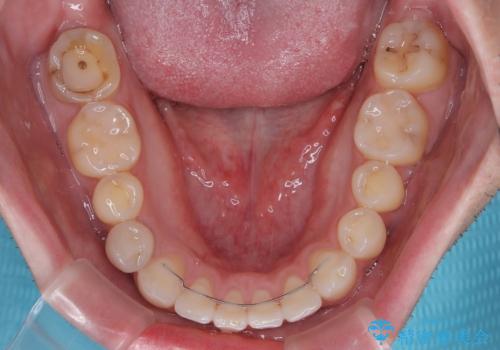

一年と数か月で矯正を終えることができました。

下顎前歯部には後戻り防止のワイヤーを装着しています。